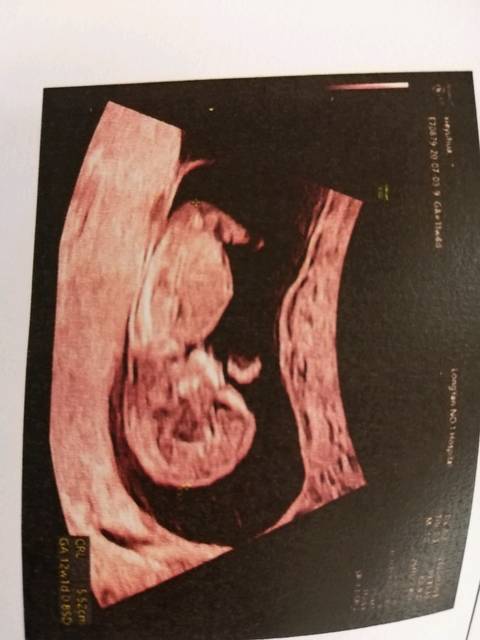

看见彩超上写着可见一胎儿雏形,把我逗乐了!

13楼 2015-7-3 孕11周 2小宝宝好可爱[爱心]心率170/分好快的呢